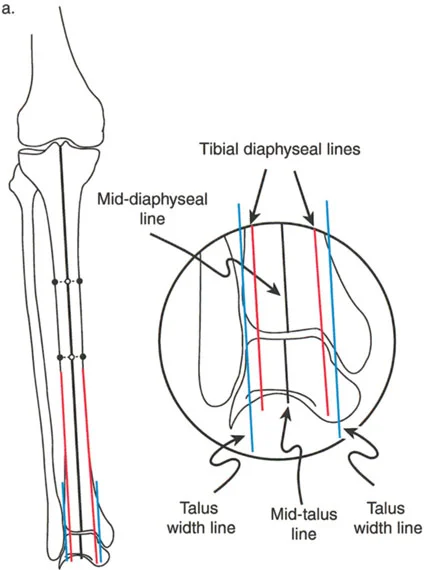

- الأشعة السينية الطويلة للطرف السفلي بالكامل أثناء الوقوف (Standing Long-Leg AP View): تُعد هذه الأشعة حاسمة لتقييم المحاذاة الميكانيكية للطرف السفلي بأكمله. تُظهر بدقة درجة الانحراف الأفحج (Varus) أو الأروح (Valgus) وتساعد في تحديد مركز دوران التشوه (CORA).

- الأشعة الجانبية الطويلة للطرف السفلي بالكامل أثناء الوقوف في أقصى بسط (Standing Long-Leg Lateral View in Maximum Extension): تُستخدم لتقييم تحدد حركة الركبة (FFD) والركبة الارتدادية (Recurvatum)، وتحديد ما إذا كان التشوه عظميًا أو ناتجًا عن تقلص في الأنسجة الرخوة.

من خلال الجمع بين الفحص السريري الدقيق والتحليلات التفصيلية للصور الشعاعية، يتمكن الأستاذ الدكتور محمد هطيف من تحديد الأسباب الكامنة وراء آلام الركبة وتشوهاتها، وتصميم خطة علاجية فردية تهدف إلى استعادة وظيفة الركبة وتخفيف الألم.